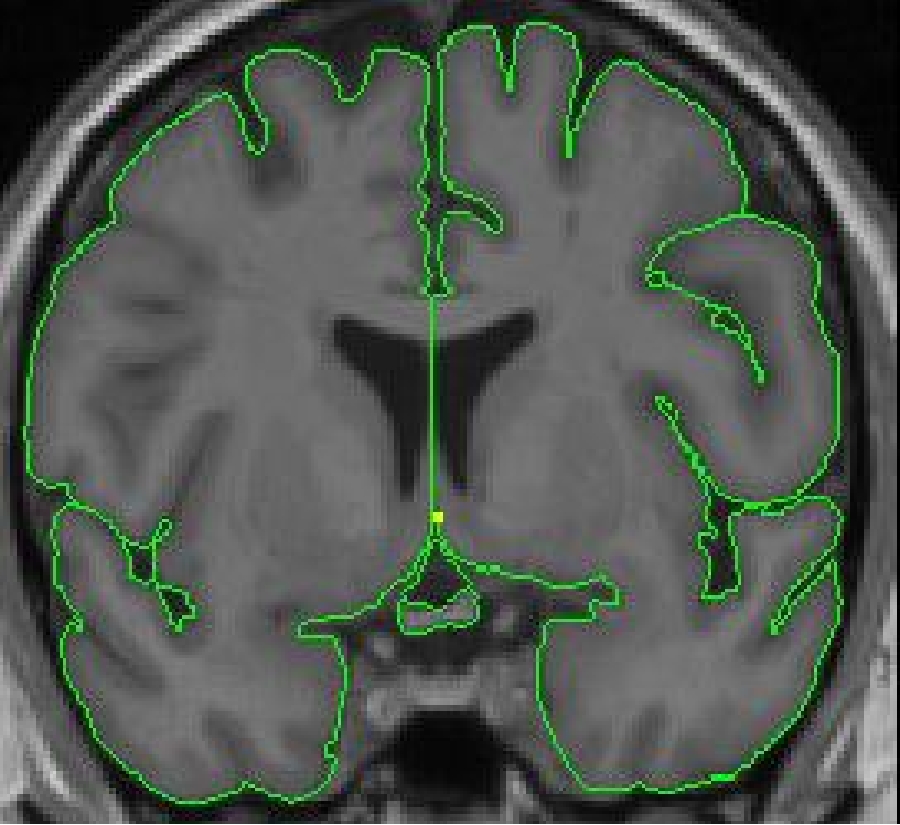

The outline for the optic chiasm is created using the intensity contour function ( press c) and manual drawing. Start segmenting the optic chiasm, from anterior to posterior, on the first slice it becomes the inferior border of the third ventricle. This is in the proximity of the coronal slice containing the anterior commissure.